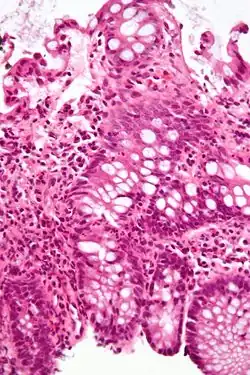

Micrograph showing intestinal crypt branching, a histopathological finding of chronic colitides. H&E stain. -

Micrograph showing crypt inflammation. H&E stain. -

Crypt abscess. H&E stain.